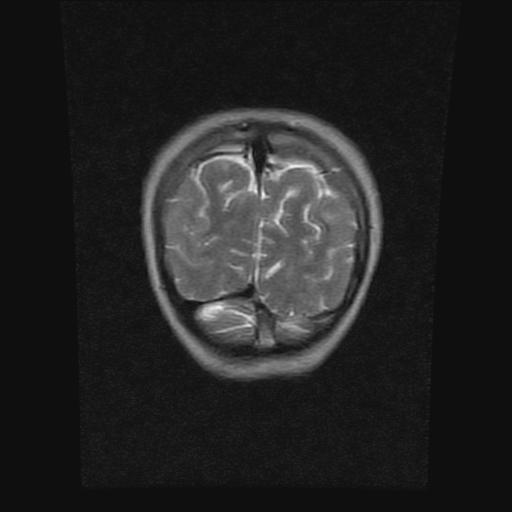

9岁女孩,三岁时诊断为癫痫,一直服丙戊酸钠,现患者一般情况良好,家长复查核磁片,看能否停药..

停药要结合临床,如无发作可以停。

停药要结合临床,如无发作可以停